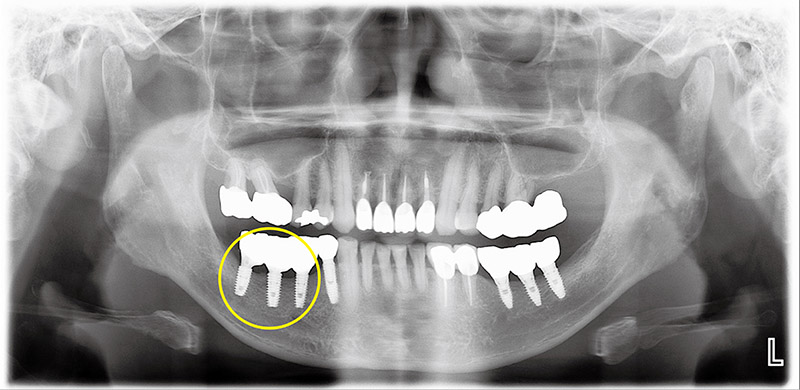

자료사진(그림1)은 식립한지 3년정도 된 임플란트 주변에서 냄새와 쓴맛이 난다고 치과에 내원한 환자다. 왼쪽아래 임플란트 나사들 주변으로 검은색 음영이 관찰되는데, 이는 임플란트 주변의뼈가 녹아있음을 의미한다.

잇몸뼈를 충분히 확보하지 않은 채 임플란트를 식립하여 불과 3년 만에 임플란트 표면이 노출되면서 주위염이 급속히 진행되고 주변의 뼈가 녹은 것으로 추정된다. 바로 옆 안쪽에서 네 번째 임플란트의 주변으로는 뼈가 비교적 온전하게 유지되고 있으나, 이것 또한 상부에 미약한 염증이 관찰된다.

결국 맨 뒤 임플란트 세 개를 제거하고 3개월이 지나 잇몸이 다 낫고 나서 충분한 높이와 두께로 다량의 골이식을 시행하였다. 또한 이식된 뼈가 주변잇몸의 압력으로 인하여 흡수되는 것을 방지하기 위해 금속막을 이용하여 공간을 형성, 6개월 후 금속막을 제거한 후 새 임플란트를 식립했다. 다음 사진(그림2)은 임플란트 식립이 완성된 상태에서 촬영한 파노라마다.